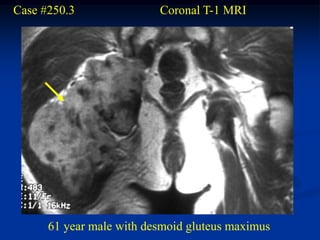

Case #250.3               Coronal T-1 MRI

61 year male with desmoid gluteus maximus

Sagittal T-2 MRI